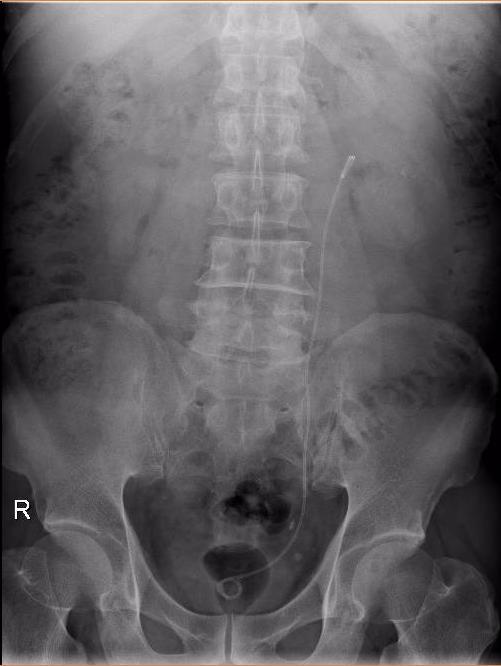

图片3.jpg

术后第一天,肾见较多碎石

完善相关检查后,积极做好术前准备在手术室全麻下行左输尿管软镜下肾碎石取石。我们采用输尿管软镜下碎块法联合快速套石法处理巨大结石(直径>3cm)获得良好的效果。该病例所示术后第一天肾区所见结石粉末化。术后3周复查KUB提示“原左肾结石已经消失,左侧输尿管支架管位置良好”。